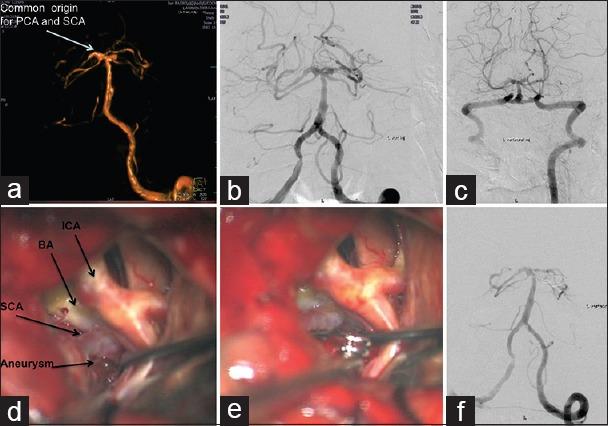

All patients with SCA were evaluated with computerized tomography angiography and/or digital subtraction angiography (DSA) prior to surgery. All patients in our series underwent microsurgical clipping and postoperative DSA to assess the extent of aneurysm occlusion. The Glasgow outcome scale (GOS) and the modified Rankin's scale (mRS) were used to grade their postoperative neurological status at discharge and 6 months, respectively.

Fourteen patients had SCA aneurysms (ruptured-9, unruptured-5). There were 10 females and 4 males with the mean age of 47.2 years (median - 46 years, range = 24-66 years). Subarachnoid hemorrhage (SAH) was seen in 11 patients. The mean duration of symptoms was 2.5 days (range = 1-7 days). The WFNS score at presentation was as follows: Grade 1 in 10 cases, II in 2 cases, III in 1 case and IV in 1 case. In the 9 cases with ruptured SCA aneurysm, average size of the ruptured aneurysms was 7.3 mm (range = 2.5-27 mm, median = 4.9 mm). The subtemporal approach was used in the first 7 cases. The extradural temporopolar (EDTP) approach was used in the last 5 cases. Complications include vasospasm (n = 6), third nerve palsy (n = 5) and hydrocephalus (n = 3). Two patients died following surgery. At mean follow-up 33.8 months (median - 25 months, range = 19-96 months), no patient had a rebleed. At discharge 9 (64%), had a GOS of 4 or 5 and 3 (21%) had a GOS of 3. At 6 months follow-up, 10/14 (71%) patients had mRS of 0-2, and 2 (14%) had mRS of 5.

14例患者患有SCA动脉瘤(破裂9例,未破裂5例)。有10名女性和4名男性,平均年龄为47.2岁(中位数 - 46岁,范围 = 24 - 66岁)。11例患者出现蛛网膜下腔出血(SAH)。症状的平均持续时间为2.5天(范围 = 1 - 7天)。就诊时的WFNS评分如下:1级10例,II级2例,III级1例,IV级1例。在9例破裂的SCA动脉瘤中,破裂动脉瘤的平均大小为7.3 mm(范围 = 2.5 - 27 mm,中位数 = 4.9 mm)。前7例采用颞下入路。后5例采用硬膜外颞极(EDTP)入路。并发症包括血管痉挛(n = 6)、动眼神经麻痹(n = 5)和脑积水(n = 3)。2例患者术后死亡。平均随访33.8个月(中位数 - 25个月,范围 = 19 - 96个月),无患者再次出血。出院时,9例(64%)患者的GOS为4或5,3例(21%)患者的GOS为3。在6个月随访时,14例患者中有10例(71%)的mRS为0 - 2,2例(14%)的mRS为5。